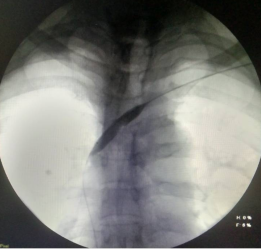

血液净化中心医生DSA下行血管造影+开通左、右无名静脉的手术过程

经过讨论,为该患者采取了DSA下使用导丝硬头配合导管锐性开通左无名静脉方案,安岳县人民医院是四川省第一个开展这一技术的县级医院。锐性开通血管风险高,面临“捅穿”血管大出血、损伤心肺临近器官风险。血液净化中心医生精心操作,成功用导丝通过闭塞部位后再使用球囊扩张导管扩张左无名静脉。

患者术后无严重并发症,术后使用原动静脉内瘘正常透析,患者眼睑浮肿、左上臂静脉曲张及静脉瘤、右颈部膨大静脉瘤消退,左上肢胀痛、头痛症状治愈,睡眠改善,生活质量明显提高。